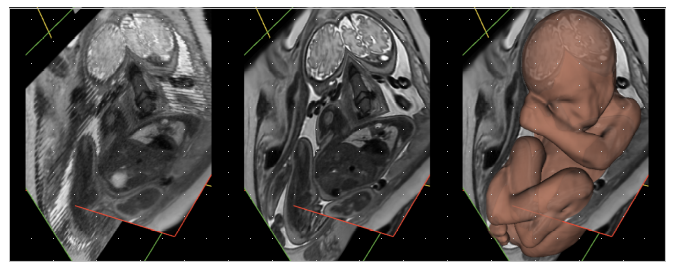

A la izquierda se muestra el resultado de una IRM fetal convencional sobre tres cortes de imagen (rojo, verde y amarillo). Se observan inconsistencias debidas al movimiento fetal. En el centro se muestran los mismos planos reconstruidos con la técnica propuesta. Se observa una mejor resolución e información consistente en 3D. A la derecha se muestra superpuesta la superficie del cuerpo fetal obtenida mediante un algoritmo completamente automático desarrollado por el estudiante de doctorado Pedro Pablo Alarcón Gil, como parte de la investigación.

La actual propuesta de los investigadores de la UPM rompe con esas limitaciones y permite desarrollar una técnica para reconstrucción de imagen fetal 3D mediante IRM con cobertura completa del útero materno. Los resultados muestran la posibilidad de obtener representaciones tridimensionales de alta calidad con cobertura completa de los tejidos fetales y del útero.

“La comparativa con métodos existentes, los cuales únicamente atienden a la consistencia 3D en regiones localizadas tales como el cerebro o el torso fetales, ha demostrado que, además de poder aplicarse a un mayor campo de visión, la técnica propuesta proporciona un incremento significativo en la resolución y calidad de imagen”, indica María Jesús Ledesma, catedrática de la ETSIT.